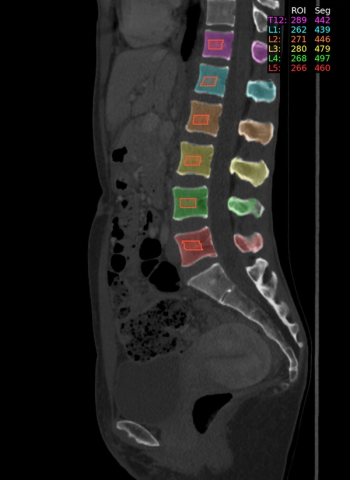

Cardiac CT angiography may provide insights on common post-op complications of left atrial appendage closure, ranging from peri-device leaks to device-related thrombus, according to research presented at the American Roentgen Ray Society (ARRS) conference.